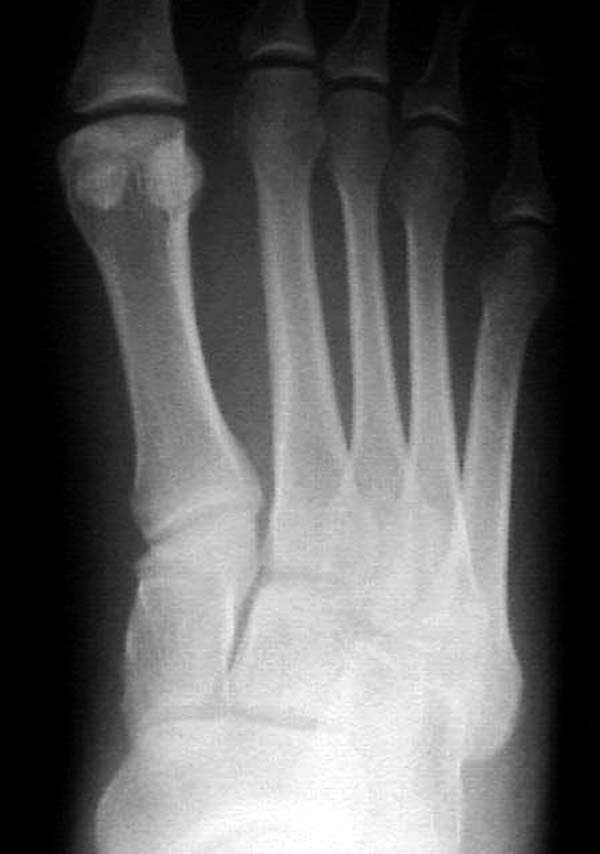

Ренген снимки прислал один из моих коллег из бывшего союза, просит совета.

К нему в клинику обратился с жалобами 24 летний

студент, получил травму две недели назад катаясь на скейтинг борд.

Ходить прихрамываяь. Небольшая отечность на тыле стопы, неврологических и сосудистых изменений нет.

Подскажите, что предпринимать больному? Снимки представлены.

Имя     : AP 2.jpg